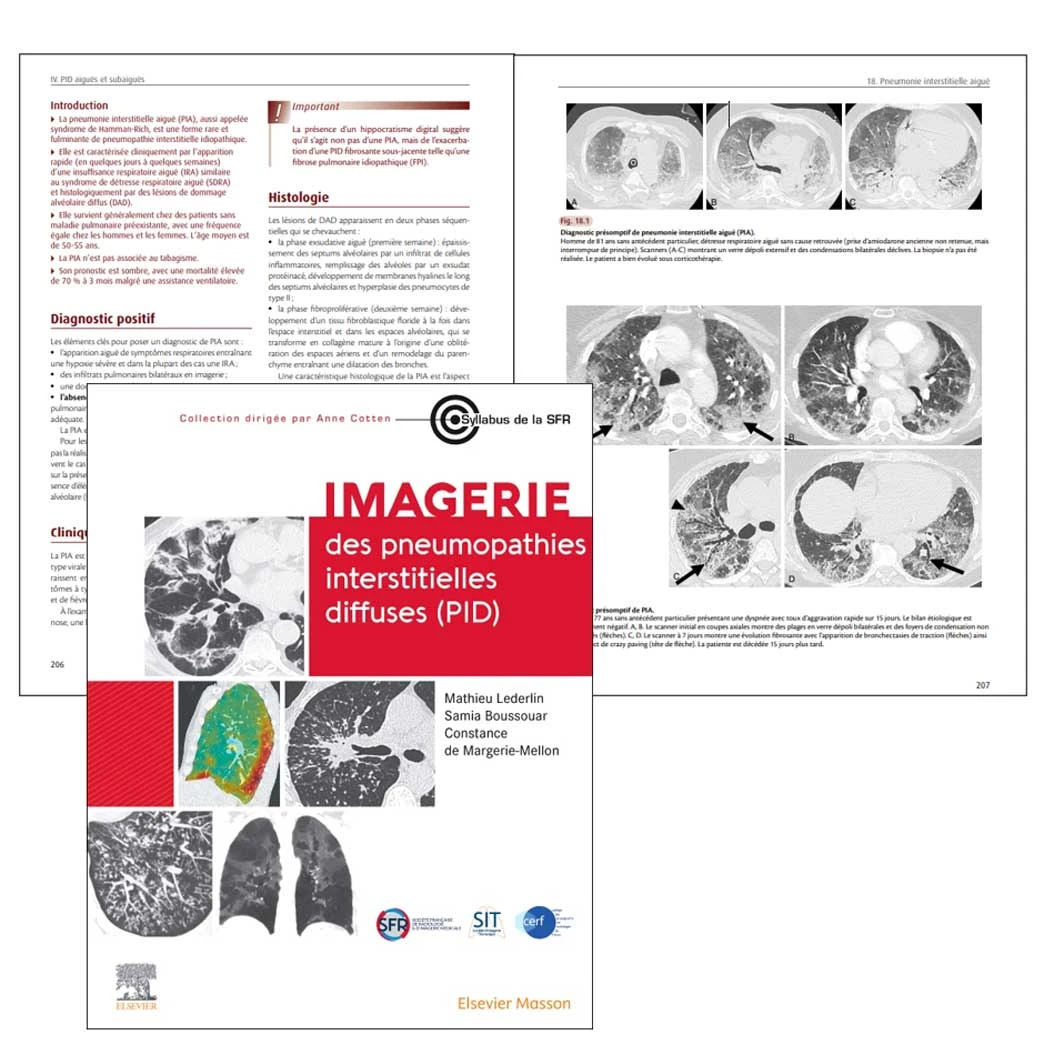

Les caractéristiques scanographiques de la PIA dérivent des lésions histologiques avec également des modifications au cours du temps. Initialement, le scanner montre des plages extensives bilatérales de verre dépoli situées dans des zones non déclives, des condensations dont la distribution évolue avec le temps : d’abord hétérogènes, patchy, elles évoluent progressivement vers des condensations gravito-dépendantes (fig. 18.1). Il s’y associe parfois du crazy paving avec une prédominance sous-pleurale. Plus tardivement, ces lésions laissent la place à des bronchectasies de traction, des opacités réticulaires, du rayon de miel et des signes de distorsion architecturale (fig. 18.2).

Fig 18.1 et 18.2